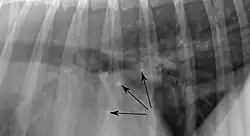

Pulmonale Osteome sind etwa 2 mm große, klar abgrenzbare, mineralisierte Knoten in der Lunge älterer Hunde. Die Anzahl und Verteilung sind variabel. Pulmonale Osteome haben keinen Krankheitswert und gelten als Zufallsbefund. Aufgrund ihrer großen Röntgendichte sind sie deutlich erkennbar. Von anderen herdförmigen Veränderungen der Lunge, wie Tumoren, lassen sie sich meist schon aufgrund ihrer geringen Größe abgrenzen, da diese in der Regel mindestens 5 mm groß sein müssen, um im Röntgen-Thorax erkannt zu werden.